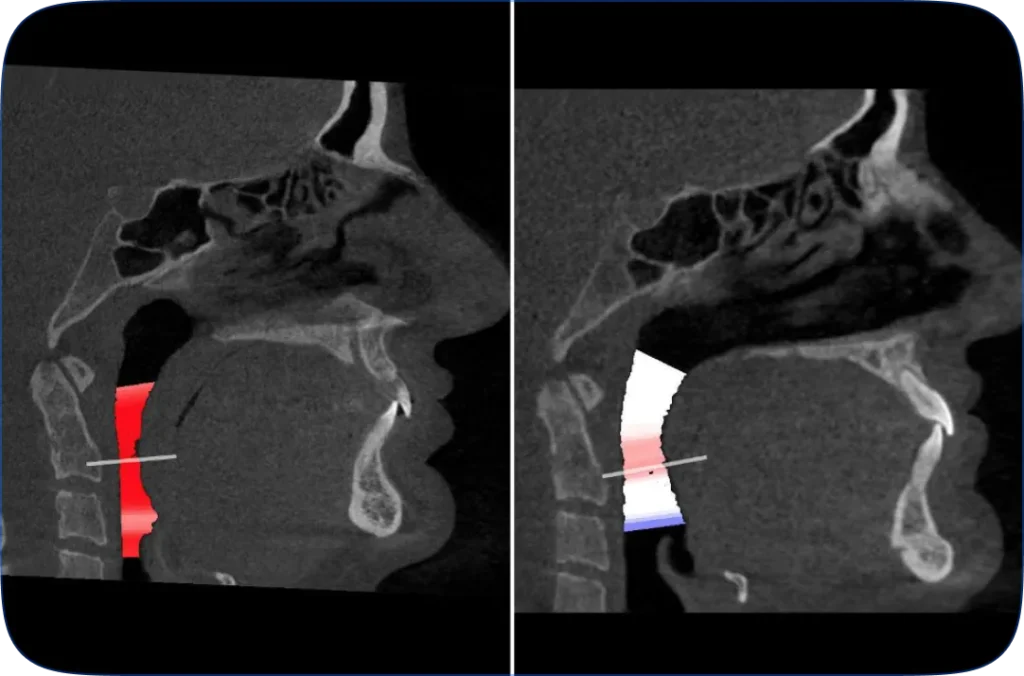

TMJ therapy to reduce chronic pain and improve balance and athletic performance